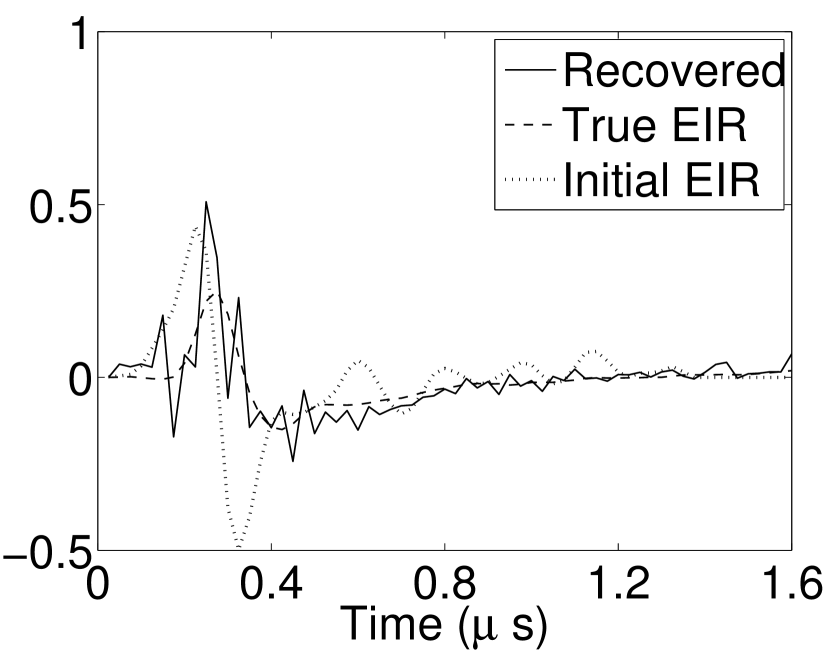

Each element in a real-world transducer array possesses its own EIR. In practice, the differences between the EIRs are sometimes neglected and an EIR corresponding to a single element may be used to represent all elements in the array. In some of the studies below, the EIR employed to initialize the VP algorithm (EIR-2 in Figure 1(b)) and the EIR employed to produce the simulated measurements (EIR-1 in Figure 1(b)) were experimentally measured from two different transducer elements in a circular transducer array (see Sec. VI-B). EIR-1 was measured by temporally integrating the PA signal produced by a point source positioned at the focus of the transducer. EIR-2 was measured by use of the method reported in [RNR2011]. In order to investigate the sensitivity of the VP algorithm to the initialization of the EIR, we employed different EIRs obtained by degrading EIR-1 as described later. When solving the sub-problem in Line-2 of Algorithm 1, was initialized as the zero vector. Algorithm 1 was terminated after 500 iterations, since it was observed that the changes in the reconstructed images with more iterations were negligible. When implemented by use of a single core of an Intel Xeon E5-2640 CPU, each iteration required approximately 7s to complete.

Figure 7(a) reveals that use of the inaccurate EIR in the conventional iterative method created strong artifacts and distortions. Figures 7(b) confirms that the artifacts and distortions were significantly mitigated when the VP method was employed. Image profiles for both cases are shown in Figures 7(c). The overall accuracy of the recovered EIR, shown in Figure 7(d) and 7(e), was improved, but it contained spurious oscillations.